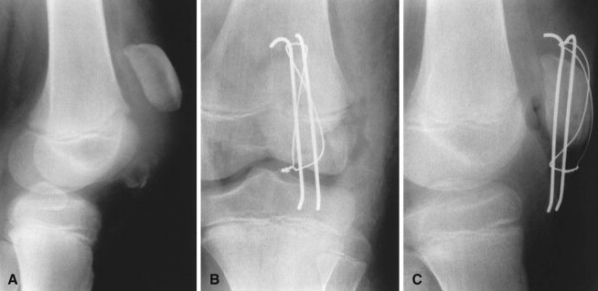

Patellar Fractures (Broken Kneecap

Patellar Fractures (Broken Kneecap

Patella Fracture | Reno Orthopedic Center direct fall on knee cap

patella hairline fracture? - Quora direct fall on knee cap